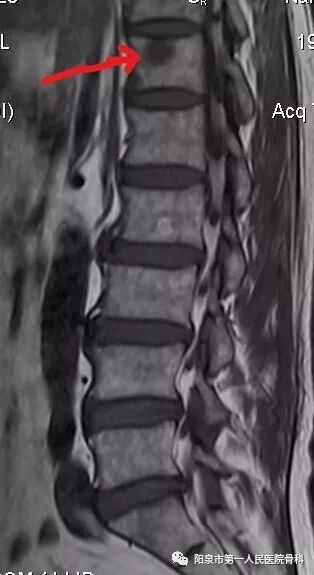

磁共振检查则可以观察到椎体内异常水肿信号,如下图黄色箭头所示,同时磁共振检查可以观察椎体后壁完整性及椎管受累情况。